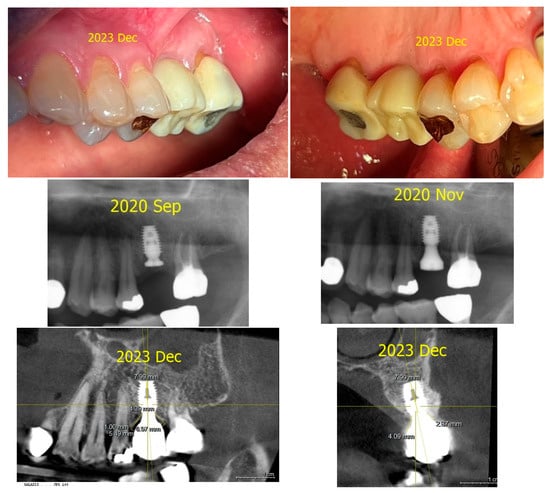

Prosthetic Management of Peri-Implant Mucositis via CRD Optimization: A Split-Mouth Case Report

Background: Subcrestally placed implants (SPIs) present advantages for bone preservation and soft tissue support but pose challenges in maintaining peri-implant soft tissue health. This case explores the role of Crest to Restoration Distance (CRD) in the development and resolution of peri-implant mucositis. Case [...] Read more.

Background: Subcrestally placed implants (SPIs) present advantages for bone preservation and soft tissue support but pose challenges in maintaining peri-implant soft tissue health. This case explores the role of Crest to Restoration Distance (CRD) in the development and resolution of peri-implant mucositis. Case Presentation: A 57-year-old woman received two SPIs—one in the upper left and one in the lower right first molar region. Despite similar implant systems and prosthetic protocols, the upper left implant developed mucositis, characterized by bleeding on probing and discomfort, while the lower right implant remained stable. Three-dimensional analysis using cone-beam computed tomography (CBCT) revealed excessive CRD at the affected site. Results: After prosthodontic revision to reduce the CRD, clinical signs of mucositis resolved, with probing depths reduced to less than 1 mm and no bleeding on probing. The control site remained healthy throughout the observation period. Practical Implications: This case highlights CRD as a modifiable prosthetic factor influencing soft tissue stability. A three-zone model—comprising the sulcus, transitional zone (TZ), and subcrestal zone (SZ)—is introduced to provide a biologically grounded framework for understanding soft tissue adaptation around SPIs. Full article